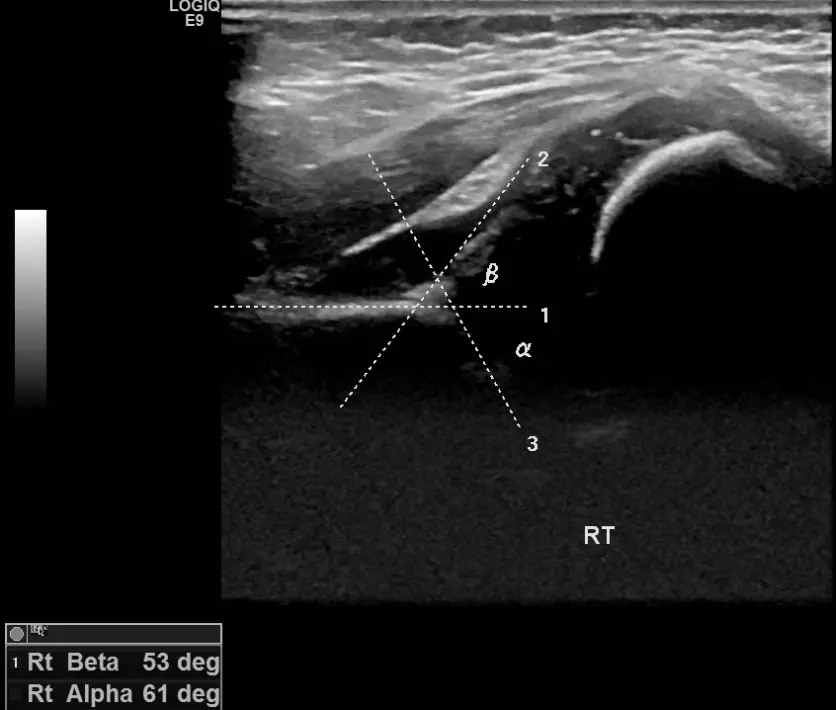

안녕하세요! 오늘은 아기 허벅지 주름이 비대칭이거나 이상하게 보일 때 꼭 체크해야 하는 내용을 알려드릴게요. 신생아나 영아의 허벅지에 자연스럽게 생기는 주름이지만, 깊이나 위치가 다르면 발달성 고관절 탈구의 신호일 수 있어요. 이 질환은 태어날 때부터 허벅지뼈가 골반에 잘 맞물리지 않는 상태로, 방치하면 걷기 어려움이나 다리 절름발이로 이어질 수 있어요. 다리 길이 차이, 다리 움직임의 이상, 걷기 시 불편함 등 증상이 있다면 빠른 검사가 필요합니다. 초음파 검사는 4주에서 6개월 사이에 가장 효과적이며, 방사선 걱정 없이 안전하게 아기 허관절 구조를 확인할 수 있어요. 조기 발견 시 간단한 치료로 정상 성장 가능하니, 아기 허벅지 주름이 이상하게 보인다면 꼭 전문가의 검진을 받아보세요. 건강한 성장과 걷기를 위해 작은 관심이 큰 차이를 만듭니다.

아기의 허벅지 주름이 비대칭이거나 다리 길이 차이, 움직임 이상이 보인다면 빠른 검진이 중요합니다. 초음파 검사는 안전하고 정확한 방법으로, 조기 치료를 통해 정상적인 성장과 걷기를 기대할 수 있어요. 부모님들이 작은 신호도 놓치지 말고 정기 검진을 챙기시는 게 좋아요.